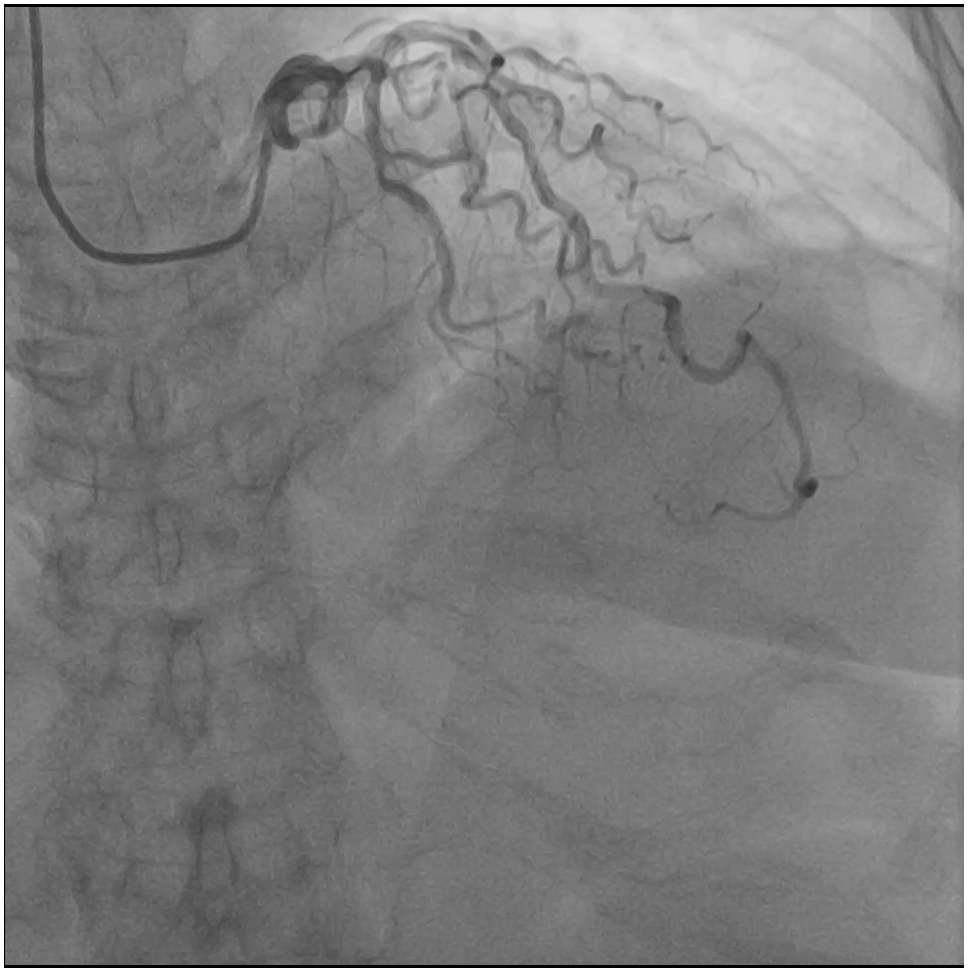

The diagnostic angiography demonstrated a severely tortuous coronary vessels, moderate lesion at LAD and LCX, total occlusion at proximal RCA with no traces of collaterals from the ipsilateral or contralateral circulations.

Several attempts to cross the lesion with workhorse wire and polymer jacketed wire with microcatheter support were failed because the wire went into small branch proximal to the occlusion. Guide catheter AL 0.75/7F was exchanged for JR 3.5/7F because of frequent pressure damping associated with deep engagement. Workhorse wire was left at the small branch while the second stiff wire was attempted to cross. The stiff wire (Gaia 2nd wire) and microcatheter was successfully cross and advanced to the distal. Microcatheter tip injection revealed contrast leakage to pericardial cavity. The stiff wire was exchanged for less traumatic workhorse wire and microcatheter was left to tampon the coronary perforation. Due to vague course of the vessel, rewiring to RCA was done with polymer jacketed wire in knuckle technique that eventually succeeded to cross the lesion and enter the true lumen. Pre-dilatation with semi-compliant balloon 2.5x15 mm at proximal-mid RCA was done to restore the flow. Angiography revealed tortuous and calcified RCA with some contrast leakage confined to pericardium. Subcutaneous fat embolization was attempted several times to seal the perforation. With minimal residual leakage, pre-dilatation with non-compliant balloon 3.0x18 mm was proceeded. Stent DES 3.0x38 mm was implanted at the proximal-mid RCA with the aid of 6F guide extension catheter. Angiography evaluation demonstrated good PCI result leaving only minimal residual contrast leakage confined to pericardium.